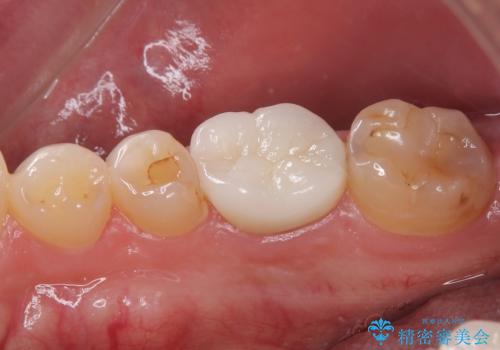

治療後特に問題もなく見た目、噛み合わせともに満足していただけました。

特に舌感が良いと喜んでくれました。

色については今後ホワイトニングをするので明るめをご希望されました。

オールセラミッククラウンは精密な型どりを行っているため、虫歯の再発リスクも少ないです。

嚙む力が強いのでマウスピースをこれから使用してもらう予定です。